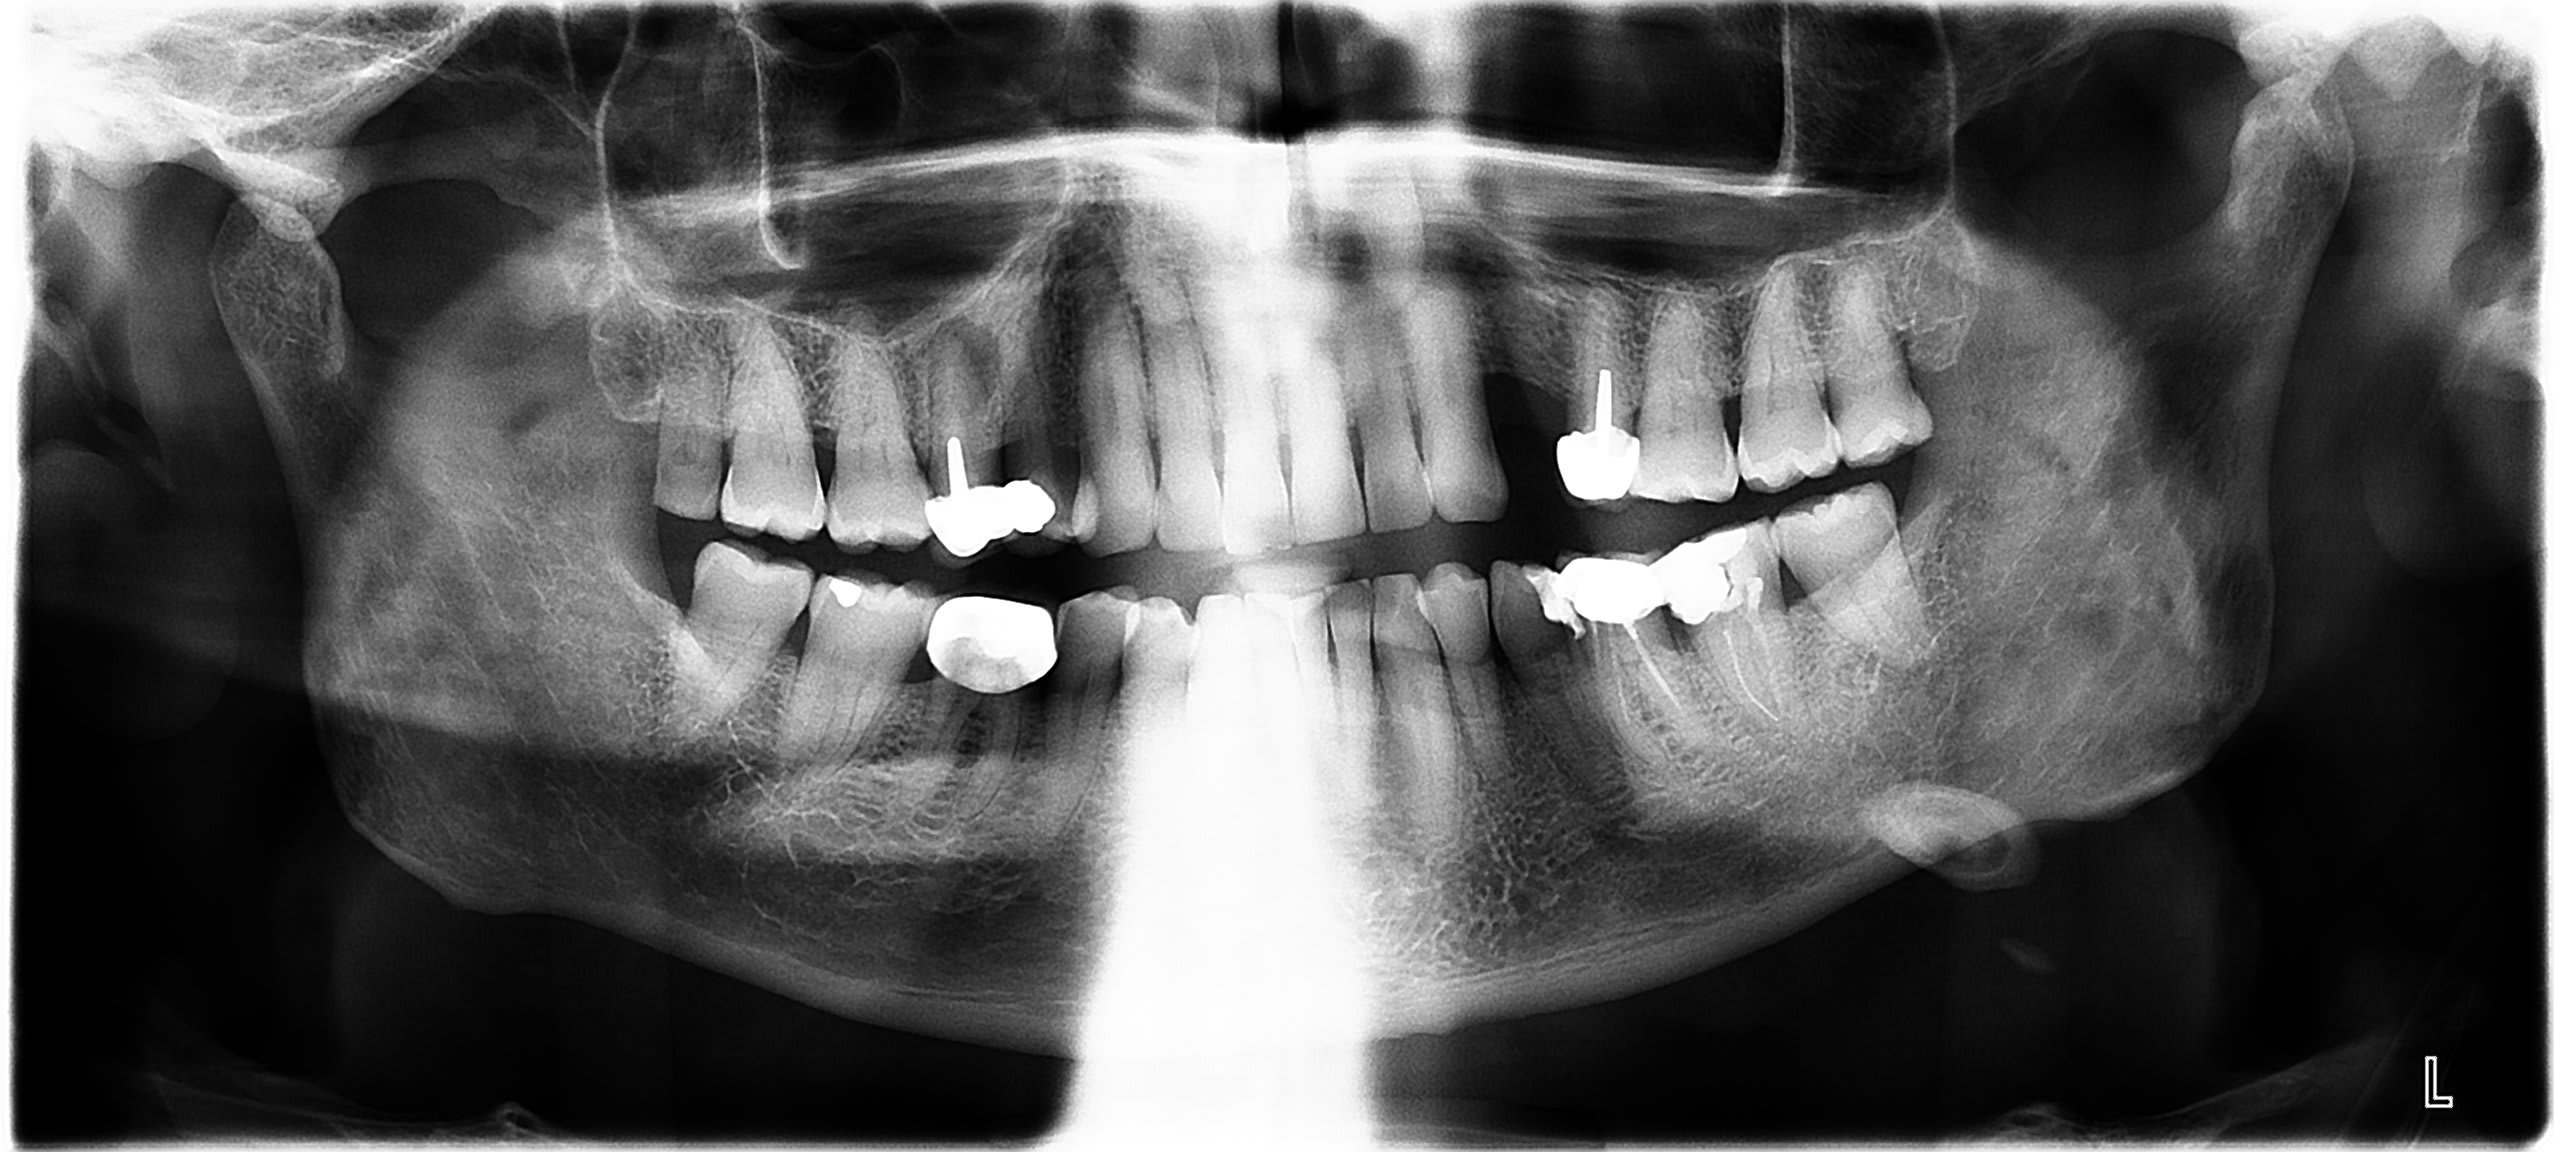

bonjour patient de 78 ans . difficulté à déglutir .douleur sous maxillaire gauche ++.

A l examen grosse adénopathie sous mandibulaire + voussure osseuse palpable du coté gauche a distance de la 37

je ne sais pas interpréter cette image mandibulaire sur la pano ( kyste calcifié , tumeur ) quelqu un pourrait il m aider merci par avance

Lithiase glande sous mandibulaire

a la palpation il y a bien une voussure osseuse coté vestibulaire. pourrait il s agir d un odontome (je dis probablement une bêtise)

la lithiase donnerait elle une image osseuse en forme d olive ? et elle ne provoquerait pas de voussure osseuse

merci à vous tous et bravo à pepito et à azerty une échotomographie a montré un calcul de la glande sous maxillaire de 7 mm.